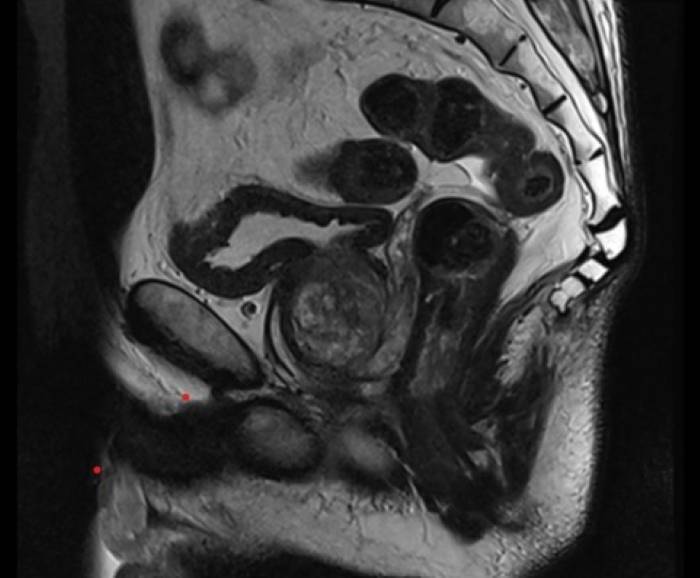

Über Magnetfelder wird ohne Strahlenbelastung das Körperinnere mit einem exzellenten Weichteilkontrast in hoher Auflösung dargestellt und ermöglicht eine präzise Beurteilung der Gewebeveränderungen.

Die MRT der Prostata erfolgt „multiparametrisch“ mit standardisierten Protokollen.

Mittels eines Bewertungssystems (PI-RADS-Score) werden die MRT-Bilder der Prostata ausgewertet und klassifiziert, als eine standardisierte Interpretation zur detaillierten Einschätzung des Prostatakrebsrisikos.

Die Prostata wird mit hochaufgelösten MRT-Bildern in allen Ebenen und mehreren Ansichten dargestellt sowie mittels verschiedener Funktionsmessungen analysiert.

Zunächst liegt der Fokus darin, in der Struktur und Signalgebung verändertes Drüsengewebe von gesundem Gewebe abzugrenzen. Als nächstes gilt es, verändertes Gewebe mit Funktionsmessungen (wie z.B. Zelldichte und Durchblutung) zu charakterisieren. Die diffusionsgewichtete MRT-Sequenz macht sichtbar, ob in verändertem Gewebe eine erhöhte Zelldichte – wie bei einem Prostatakarzinom – vorliegt. Die dynamische kontrastmittelangehobene MRT-Sequenz lässt Prostatakrebsareale mit einer erhöhten Durchblutung abgrenzen.

Als eine nicht-invasive Methode ist die MRT der Prostata eine schonende und völlig schmerzfreie Untersuchung, die frühzeitig eine Unterscheidung zwischen bösartigen, entzündlichen oder leichten Prostataveränderungen ermöglicht. Unabhängig der Prostatagröße ist die gesamte Prostata präzise beurteilbar und gewährleistet sogleich ein „Staging“ möglicher Prostatakrebsherde bezüglich Lage, Größe, Charakteristika und Ausbreitungsgrad.

Die multiparametrische MRT ist hierbei bildgebend die genaueste Methode im Nachweis von therapiebedürftigem Prostatakrebs, dass bei frühzeitiger Diagnose gute Heilungschancen hat. Sie liefert entscheidende Hinweise zur sodann ggf. gezielten Punktion der Prostata und Behandlung der Erkrankung.